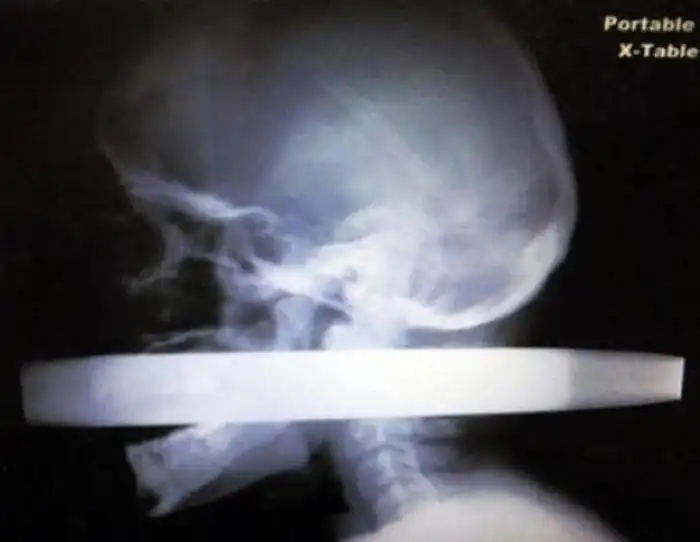

На рентгеновских снимках людей порой можно обнаружить самые необычные предметы, которые находятся в их теле.